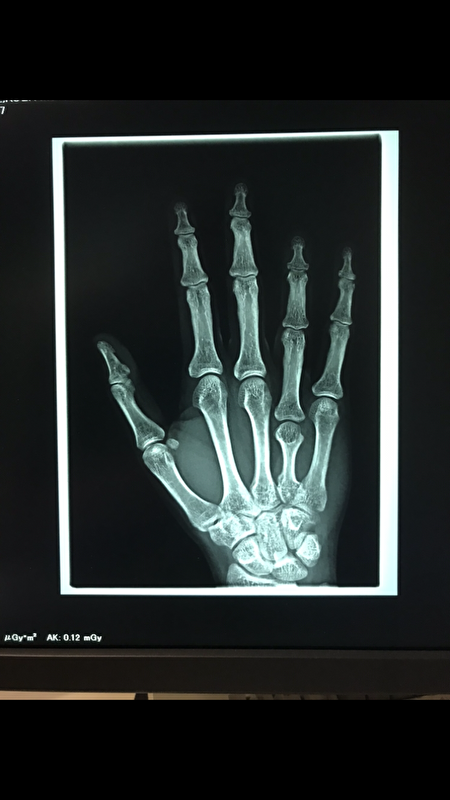

dit was de rontenfoto:

resultaat operatie van 3 uur om platje te bevestigen,20 week met 2 krukken en een jaar fysio hij zal nooit meer 100% worden.

1 geluk is toen ik op de eerste hulp lag in het ziekenhuis zeiden ze "ik hoop dat je ooit weer pijnvrij loopt" en dit is op een normale dag wel zo, bij teveel belasting gaan hij mopperen en zeuren.

op mijn knieën zitten en kruipen is wel verleden tijd.